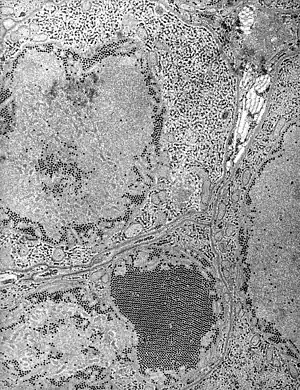

Electron micrograph of "Saint Louis encephalitis virus" seen in a mosquito salivary gland | |